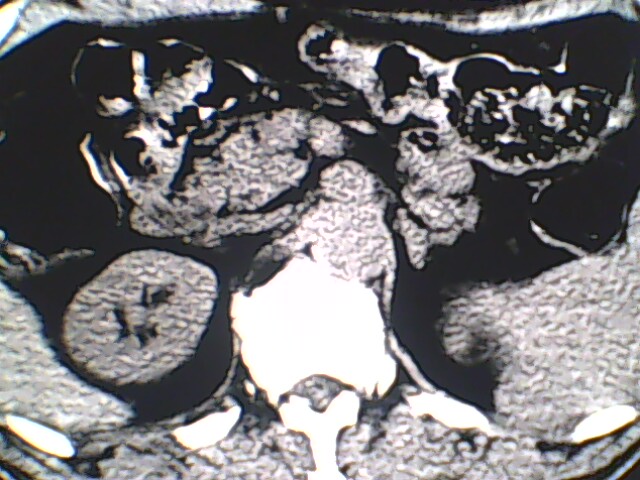

男,56岁,高血压,临床怀疑肾上腺问题,肝脏怎么那么高啊?能描述一下么?

右侧膈膨升,间位结肠,胸腰椎退行性骨关节病,右侧肾上腺可疑增生(图像颗粒太粗,窗太窄,不好看)。

支持 右侧膈膨升,间位结肠;胸腰椎退行性骨关节病;双侧肾上腺可疑增生。